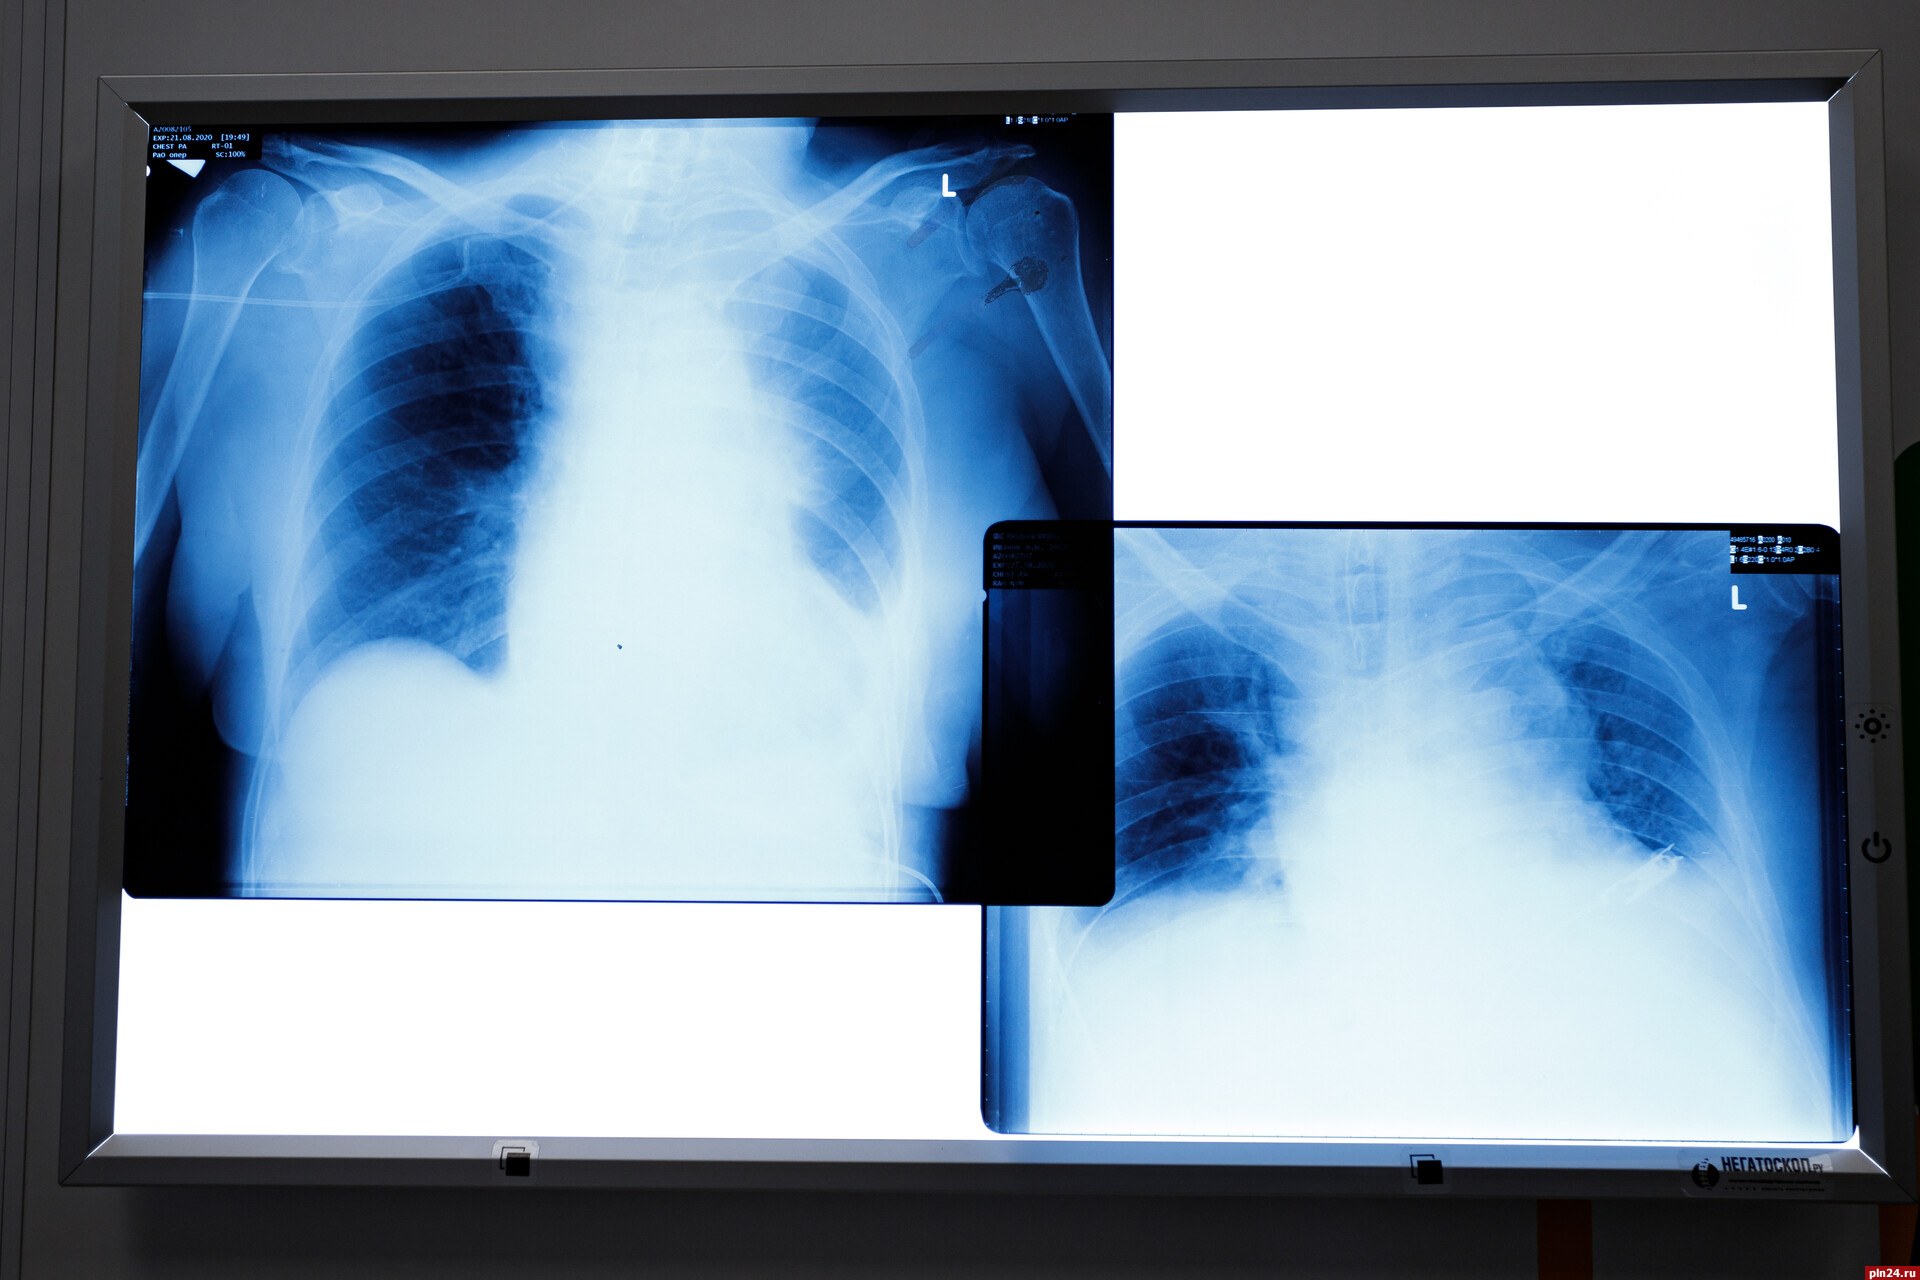

Фото из архива ПЛН

Ежегодно 24 марта отмечают Всемирный день борьбы с туберкулезом. Его цель - привлечь внимание общественности к профилактике заболевания и расширить противотуберкулезную деятельность. Псковское региональное отделение Российского Красного Креста совместно с противотуберкулезным диспансером Псковской области проводит мероприятие, направленное на профилактику туберкулеза для жителей города Пскова в возрасте старше 18 лет, которые не проходили флюорографию более года.